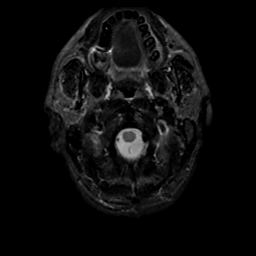

MR Study #20 October 6, 1991 -- Slice #1